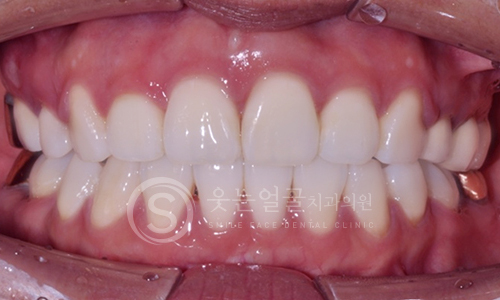

한눈에 보는

치아교정 전후사진

웃는얼굴치과의 투명교정은 투명한 재질의 장치로

티가 거의 나지 않아 심미적으로 매우 우수하며,

내원 횟수를 줄여 보다 편하게 치료 받으실 수 있습니다.